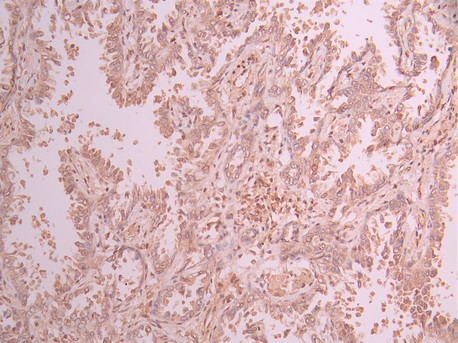

IHC image of CSB-RA145805A0HU diluted at 1:100 and staining in paraffin-embedded human lung cancer performed on a Leica BondTM system. After dewaxing and hydration, antigen retrieval was mediated by high pressure in a citrate buffer (pH 6.0). Section was blocked with 10% normal goat serum 30min at RT. Then primary antibody (1% BSA) was incubated at 4°C overnight. The primary is detected by a Goat anti-rabbit polymer IgG labeled by HRP and visualized using 0.05% DAB.